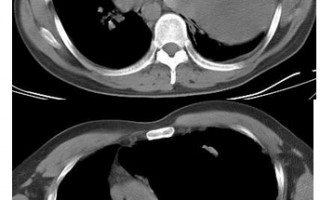

CT减影技术,ct减影处理方法 ⟨技术原理⟩CT减影技术通过数字差分处理消除非管结构干扰,其心流程为:双期扫描:先获取平扫(蒙片),再注射对比剂进行增扫描[[1]... 用户投稿 2025-05-31 41